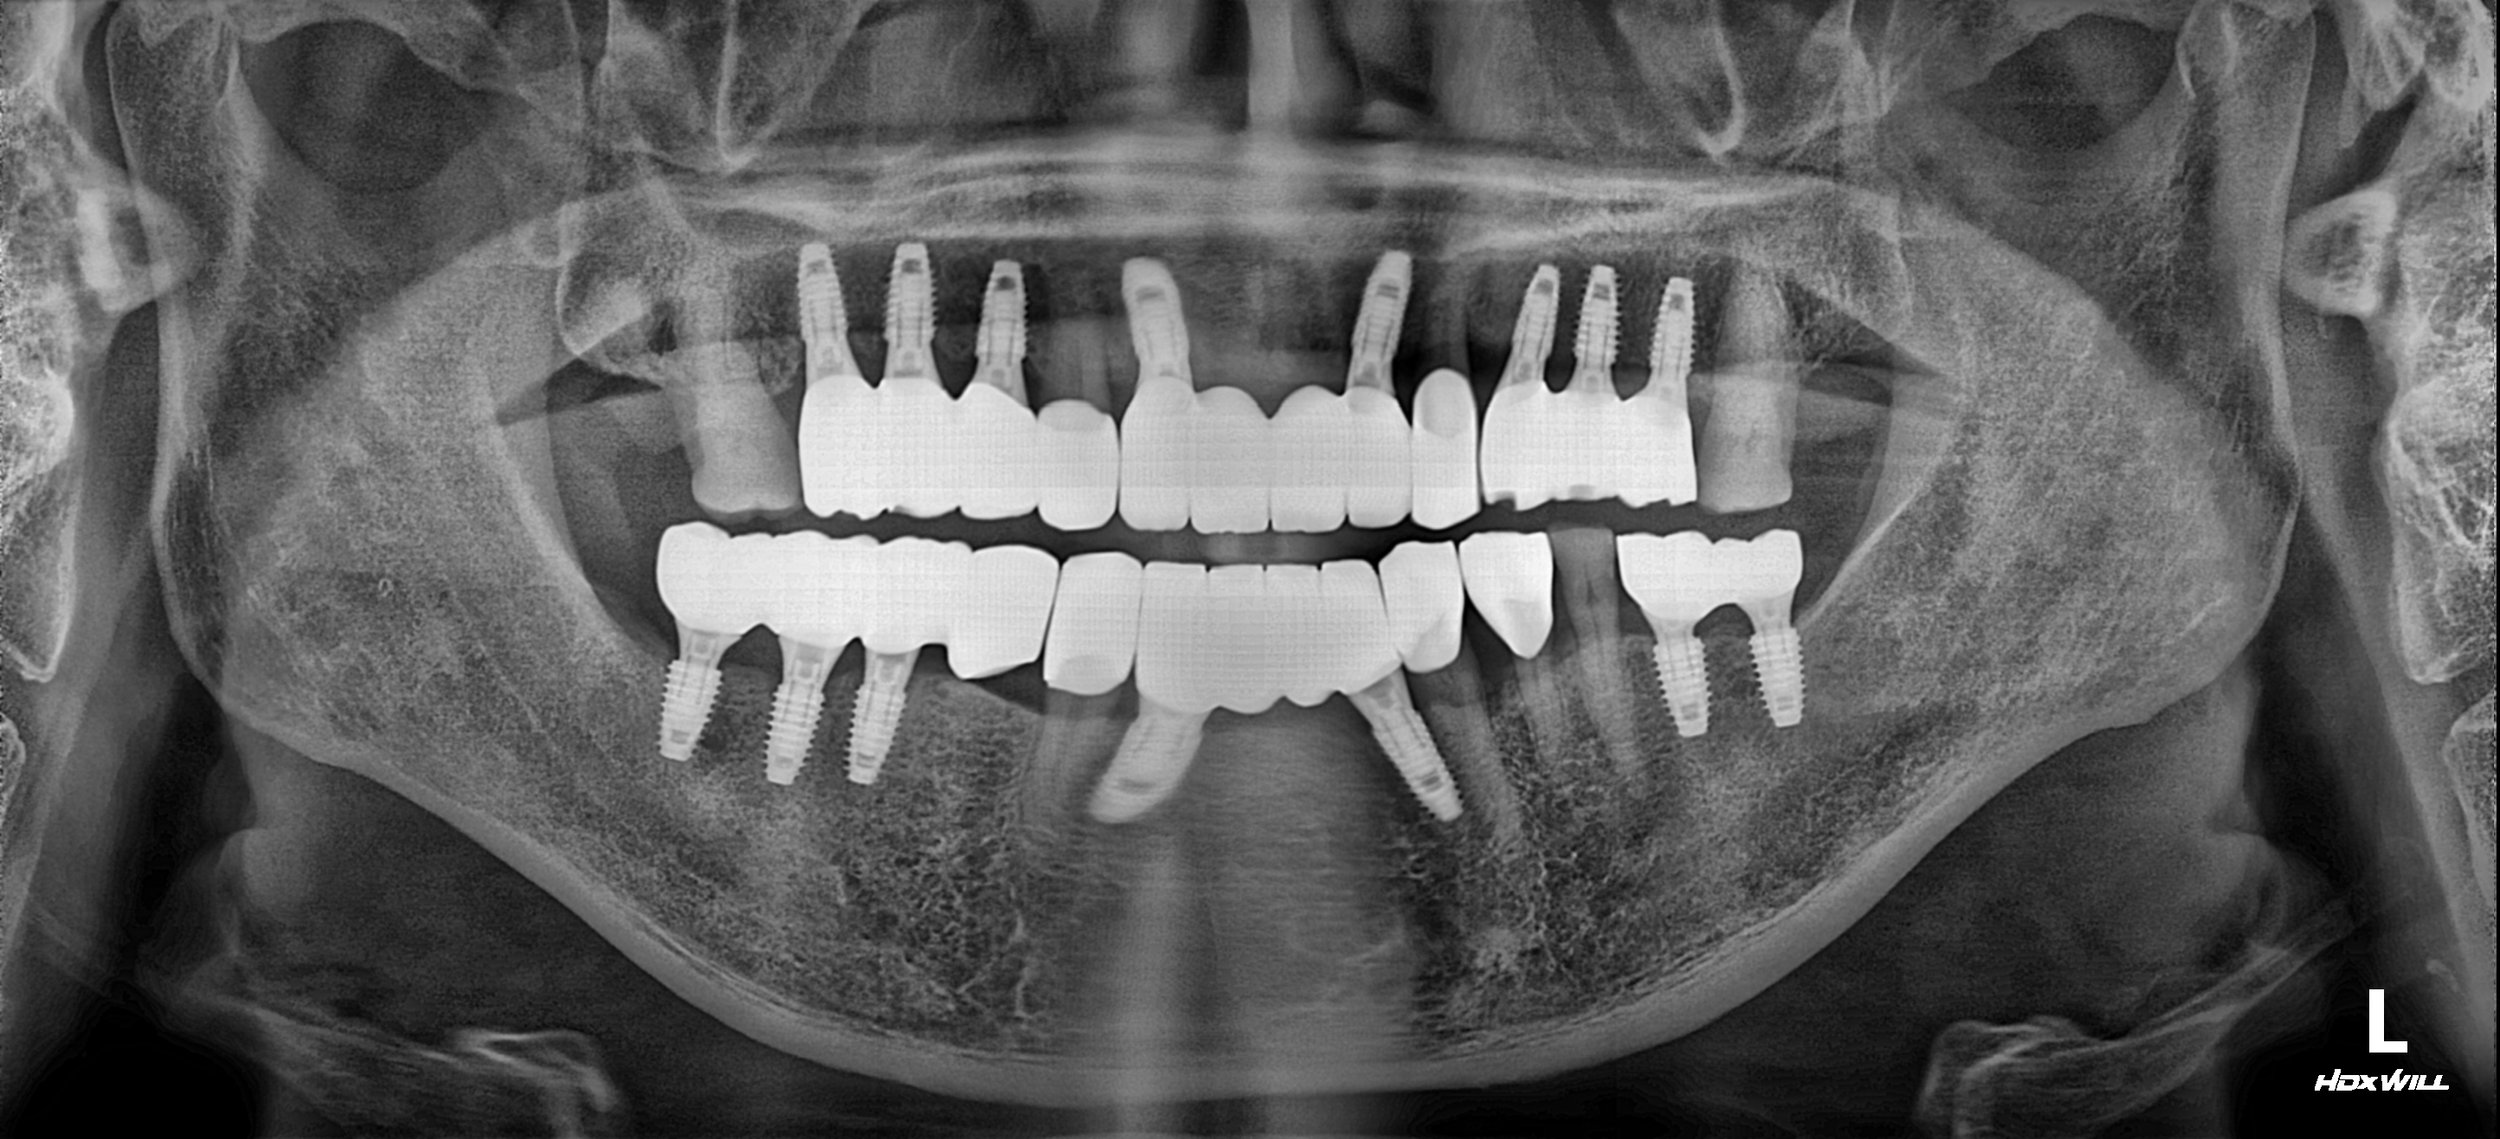

• Strategic Implant Integration: To place implants in key edentulous areas to provide the necessary posterior support that natural teeth alone could no longer provide.

2. Implant Phase: Dental implants were strategically placed in the posterior segments. This provided the "occlusal stops" required to prevent overloading the remaining natural teeth.

3. Prosthetic Reconstruction: Rather than a unified full-arch prosthesis, a combination of implant-supported bridges and tooth-supported crowns was utilized. This hybrid approach allowed for the preservation of the patient's biological proprioception (natural tooth feel).

The final result is a stable, functional, and aesthetic reconstruction that honors the patient's biological integrity while providing the structural support of modern implantology.